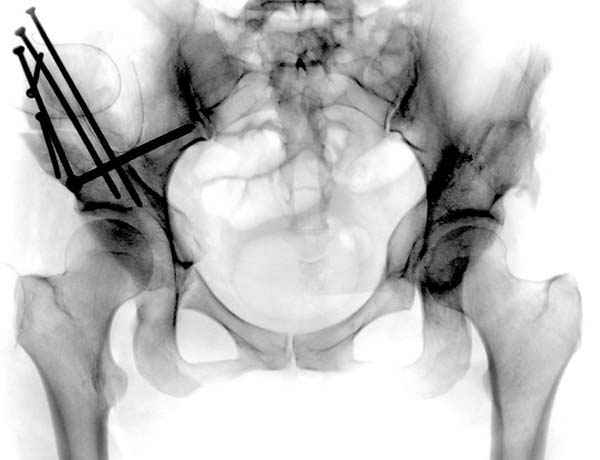

Рис.1 Трехмерная модель тазобедренного сустава с аналогом связки головки бедра. Заметно, что из торца головки выходит капроновый шнур, который с одной стороны прикрепляется к ножке бедренной части модели, а другой его конец, проходя через головку и прикрепляется к вертлужной части модели. Динамометр оказывается не нагруженным, так как аналог связки головки бедра замыкает подвижный узел модели во фронтальной плоскости.